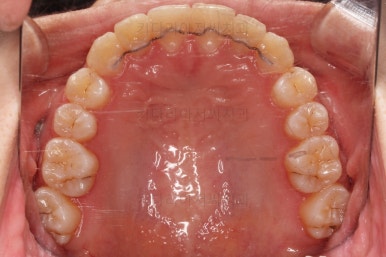

덧니가 완전히 개선디ㅗ었고 필요한 충치치료도 부분적으로 진행했고요.

중앙선이나 교합도 양호하게 마무리 했습니다.

환자분이 원하는 포인트들이 다 개선되었고요.

충치도 틀린그림 찾기 수준으로 진짜 필요한 몇 개만 치료를 하고 연산동교정치과 마무리를 했습니다. 어차피 유지관리 체크를 꾸준히 내원하실 거기 때문에 지켜보기로 했습니다.